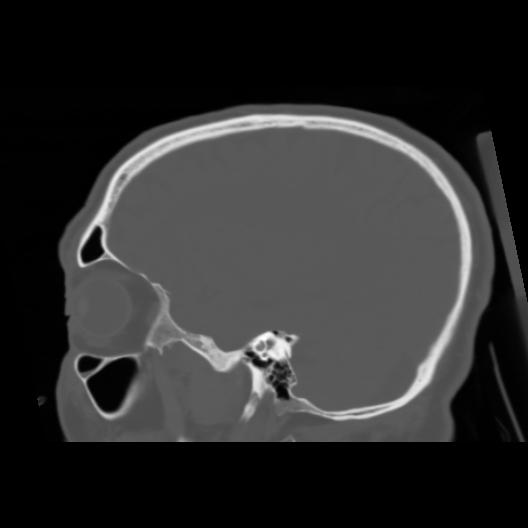

6 CEREBRO,,Sagittal,3.000,CEREBRO,Sagittal,